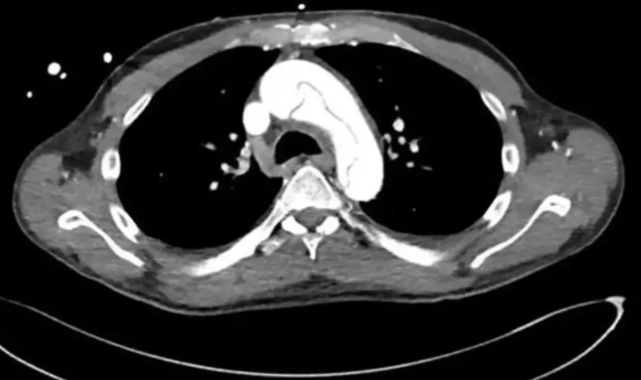

Amerika'da 59 yaşındaki bir erkek, mastürbasyon sonrası ciddi bir sağlık sorunu yaşadı. Adam, kendi kendini tatmin ettikten sonra çenesinde sıkışma ve ellerinde karıncalanma hissederek ambulans çağırdı.Hastaneye vardığında, doktorlar başlangıçta sepsisten şüphelendi. Ancak yapılan testler, aslında aort damarında bir yırtık olduğunu ortaya çıkardı. Bu durum, aort yetersizliği adı verilen ciddi bir kalp acil durumuna yol açtı.Aort diseksiyonu olarak bilinen bu durum, genellikle göğüs veya sırtta keskin bir ağrı, nefes darlığı ve aşırı terleme gibi belirtilerle kendini gösterir. Ancak bu vakada, hasta bu tipik belirtilerin hiçbirini yaşamadı. Bu durum, vakayı daha da ilginç ve tehlikeli hale getirdi.Hastanın tıbbi geçmişinde yüksek tansiyon, nadir bir pankreatit türü ve kronik böbrek yetmezliği vardı. Ancak sağlık sorununu yaşamadan bir gün önce 5 kilometrelik bir koşu yapmıştı.Hastaneye geldiğinde, aşırı düşük kan basıncı ve yavaş nabız tespit edildi. Ultrason taraması, aortun üst kısmında bir yırtık olduğunu gösterdi. Bu durum, acil açık kalp ameliyatı gerektiren hayati bir tehlike oluşturuyordu.Adam, aort grefti değişimi ameliyatı geçirdi ve iyileştiği bildirildi. Ancak doktorlar, mastürbasyon ile aort yırtılması arasındaki bağlantının tam olarak anlaşılamadığını belirttiler. Kronik pankreatitin önemli bir risk faktörü olabileceğini düşünüyorlar.Bu vaka, aort diseksiyonunun her zaman tipik belirtilerle ortaya çıkmayabileceğini gösteriyor. Doktorlar, ağrısız aort diseksiyonlarının nadir görüldüğünü ve genellikle daha yüksek ölüm riski taşıdığını vurguladılar.Sonuç olarak, bu vaka tıp dünyasına önemli bir hatırlatma yapıyor: Sağlık sorunları her zaman beklenen şekilde ortaya çıkmayabilir ve her hastanın durumu dikkatle değerlendirilmelidir.